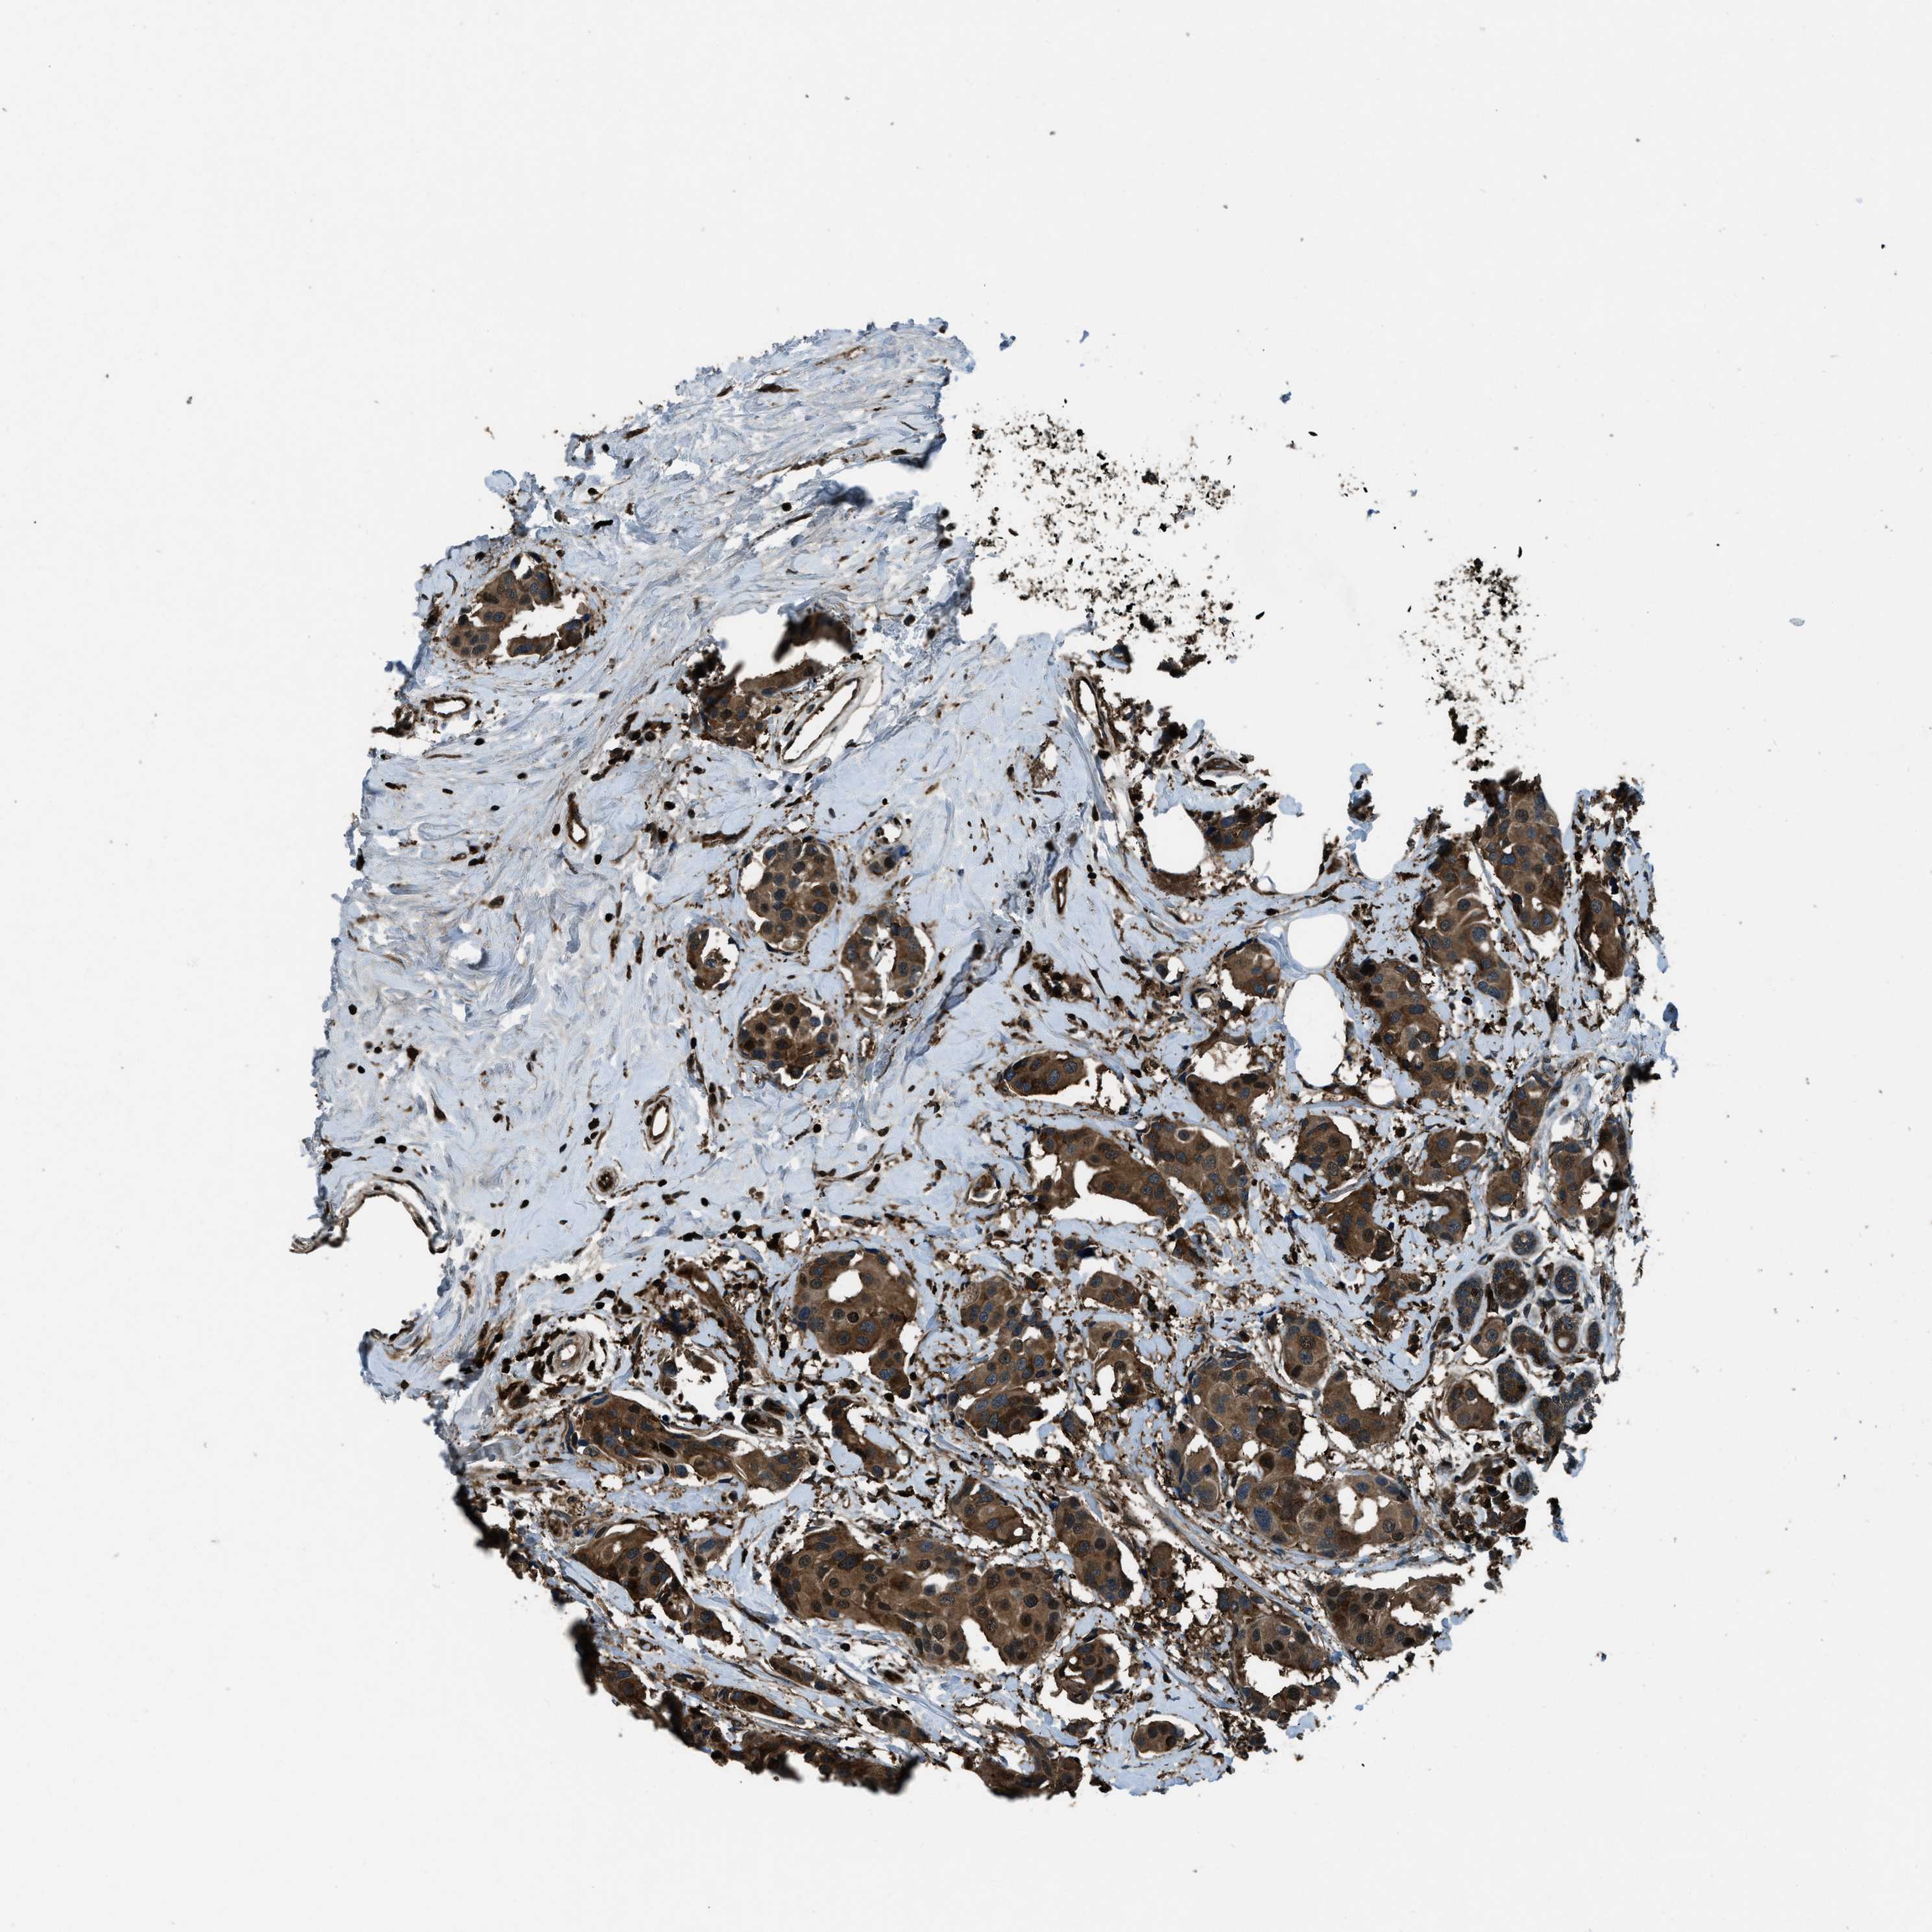

CANCER BREAST CANCER Show tissue menu

BRCA TCGA BRCA VALIDATION PROTEIN EXPRESSION